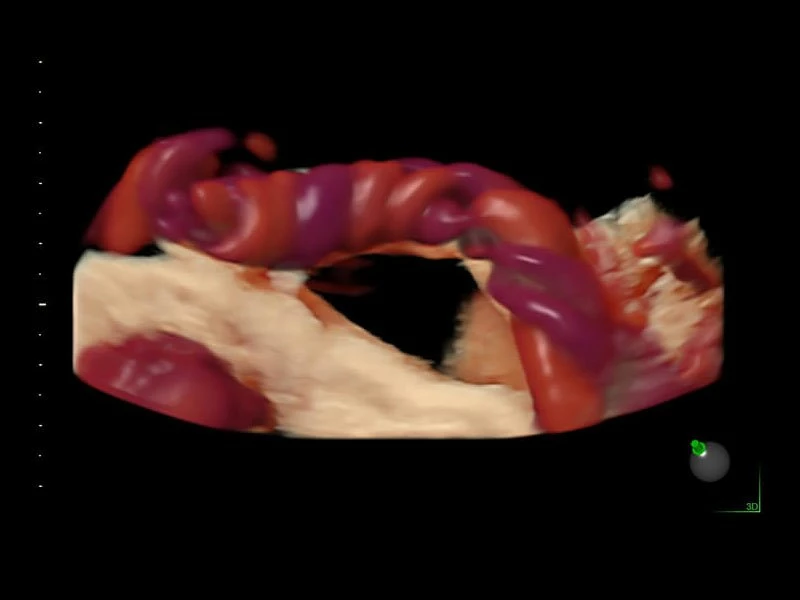

Объемное сканирование Voluson — 3D/4D вашей мечты

Объемное УЗИ на Voluson E10 — это не просто потрясающе красивая картинка, это ценный инструмент получения дополнительной информации при обследовании женщин.

Voluson E10 поддерживает инновационные технологии формирования изображений — HDlive Silhouette и HDlive Flow, которые позволяют увидеть мельчайшие детали. Алгоритм SonoRenderlive упрощает рабочий процесс и дает возможность реконструировать изображение поверхностей, определяя область перехода между тканью и жидкостью.

- HDlive

Инновационная технология визуализации HDlive обеспечивает получение реалистических изображений за счет эффекта объемного зрения, повышая достоверность клинической оценки. Теперь режим HDlive дополняют две новые функции:

- Технология HDlive Silhouette — задает разный уровень прозрачности, помогая выявлять контуры внутренних структур и точнее оценивать состояние плода в первом триместре.

- Технология HDlive Flow — повышает реалистичность визуализации сосудистых структур, улучшая восприятие глубины (по сравнению с традиционным цветовым допплером и функцией HD-Flow).